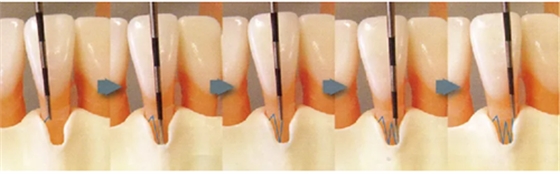

● 步行式牙周探诊的操作

牙周探针的工作尖始终与牙体接触,将工作尖从袋底上提1~2mm的幅度进行步行式探诊。